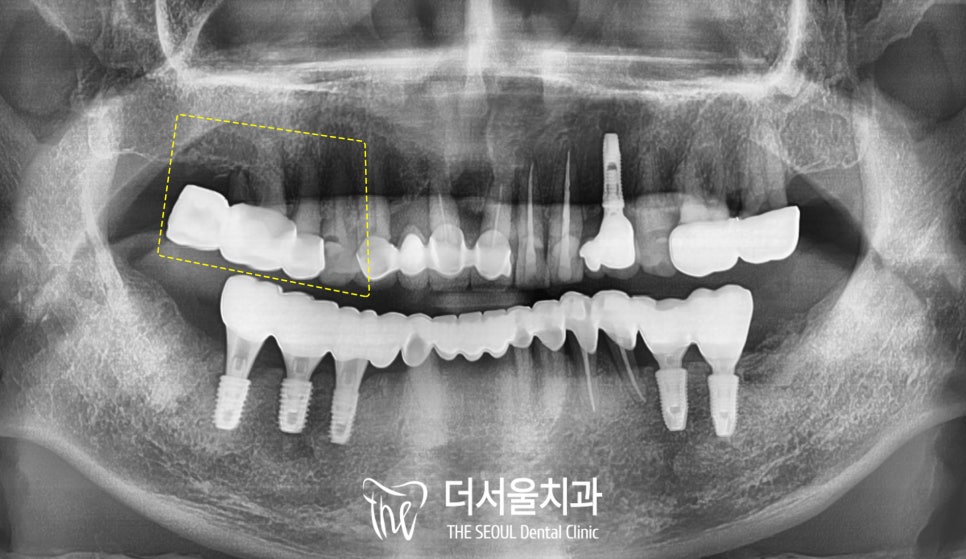

2. 파노라마 엑스레이 촬영 및 진단

성남 치과 에서

파노라마 엑스레이를 찍어

전체적인 구강 상태를

확인해 보았습니다.

이전에

캔틸레버 브릿지라고 하여

한쪽에만 지대치를 둔 방식으로

보철을 씌워두신 것이 보였으며,

예상했던 대로 #14는

인접면 우식이 생겨있었습니다.

이미 보철 하방으로

치조골 소실도 심하고, 충치도 깊었기에

더서울에서 내린 진단은 다음과 같습니다.

★ Tx plan

1. 전악 스케일링

2.#14 endo crown

3. #15=17 old bridge 제거

4. #15 내부 상태 확인 후

re-cr or endo crown

5. #16=17 implant bridge